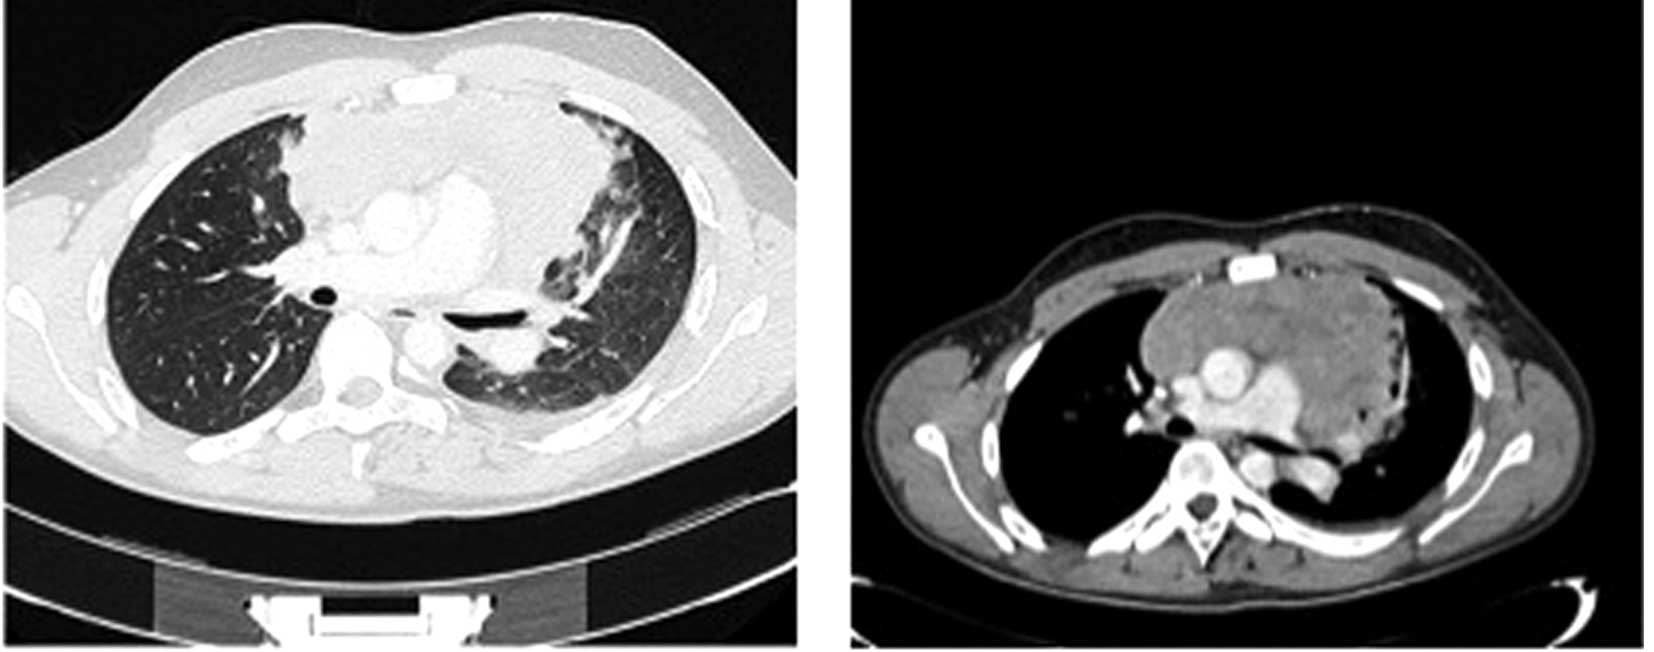

CT examination showed multiple mediastinal lymph nodes with internal liquefactive necrotic phenomena; lymphadenopathy was extended to the bronchovascular structures and to the esophagus, causing a significant reduction in the diameter of the tracheal lumen on the superior mediastinum (Fig. 3). In addition, CT indicated compression of the SVC, infiltration of the right pulmonary artery, moderate pericardial effusion and bilateral pleural effusion (Fig. 3). The patient was administered palliative care, including physiologic salt solution, and morphine (4 mg; Mundipharma Pharmaceuticals srl, Milan, Italy) and methylprednisolone (40 mg; Pfizer srl, Milan, Italy) intravenously. The patient succumbed to acute respiratory failure after 4 days.

Figure 3.

Axial computed tomography with a contrast agent in the mediastinal window (right) and in the parenchymal window (left) shows multiple lymphadenopathy with marked necrotic phenomena inside, occupying the mediastinum; the lymph nodes extend towards all the bronchovascular structures and to the esophagus causing a significant reduction in the tracheal caliber in the superior mediastinum. Compression of the superior vena cava and infiltration of the right pulmonary artery is observed.